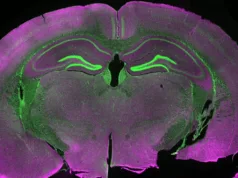

Pentru a înțelege fenomenul, trebuie să privim procesul obișnuit de reproducere umană. Totul începe când celulele sexuale (gameții) – ovulul și spermatozoidul – fuzionează la fertilizare. Fiecare gamet conține jumătate din numărul standard de cromozomi, astfel încât embrionul rezultat primește un set complet. La om, vorbim de 46 de cromozomi, organizați în 23 de perechi.

Acel ADN nu rămâne perfect static. Din momentul concepției, de-a lungul dezvoltării embrionare și pe tot parcursul vieții, se acumulează mici erori de copiere și mutații. Deși majoritatea sunt inofensive, unele pot dicta riscul pentru anumite boli mai târziu în viață. Totuși, oricâte mutații ar apărea în timpul diviziunii celulare, ele nu vor genera niciodată o secvență ADN complet diferită.

Deci, cum ajunge o persoană precum Lydia Fairchild să dețină un set de ADN într-o parte a corpului și un altul, total distinct, în alta? Răspunsul stă într-un fenomen numit himerism tetragametic.

Aici intervine partea cu adevărat fascinantă: uneori, în stadiile incipiente de dezvoltare în uter, unul dintre acești doi embrioni îl poate înlocui și, literalmente, absorbi pe celălalt. Cunoscut sub numele de „sindromul gemenului dispărut”, acest proces poate avea loc fără ca mama să bănuiască vreodată că a purtat doi embrioni. În consecință, copilul care se naște nu are de unde să știe că a avut cândva un frate sau o soră, al cărui material genetic a devenit acum o parte integrantă din propriul său corp.